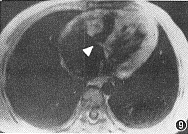

4. MRI:显示右室心腔小,心肌呈中等信号,其中有1例三尖瓣环狭窄,右心房和左心室增大(图9)。

, 百拇医药 图9 MRI横断面:右室心腔变小,三尖瓣环狭窄(箭头)、心肌呈中等信号,右心房和左心室增大